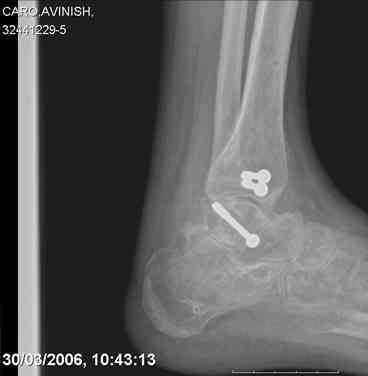

ya by popytalsya sobrat talus anatomichno,seichas pozdno operirovat iz za oteka,po etomy distrakziya apparatom budet optmalna.Posyalu vam podobyai moi sluchai.

Mark, судя по снимкам в день поступления произведен А.В.Ф., а остеосинтез ч-з какое время произведен?, остеосинтез произвели открытым способом?( на снимке п/о рубцы).

aparat postavlen v den postupleniya,rastaynuli, vpravili zakryto naskolko vozmoghno, a kogda otek spal sdelali otkrytoe vpravlenie.Teryat tut nechego, moghno tolko uluchshit.

Udachi.

Mark Eidelman